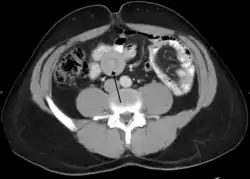

An intussusception is often suspected based on history and physical exam, including observation of Dance's sign. A digital rectal examination is particularly helpful in children, as part of the intussusceptum may be felt by the finger. A definite diagnosis often requires confirmation by diagnostic imaging modalities. Ultrasound is the imaging modality of choice for diagnosis and exclusion of intussusception, due to its high accuracy and lack of radiation. The appearance of target sign (also called "doughnut sign" on a sonograph, usually around 3 cm in diameter, confirms the diagnosis. The image seen on transverse sonography or computed tomography is that of a doughnut shape, created by the hyperechoic central core of bowel and mesentery surrounded by the hypoechoic outer edematous bowel.[10] In longitudinal imaging, intussusception resembles a sandwich.[10] It is also called "pseudokidney" sign because hyperechoic tubular centre is covered by a hypoechoic rim producing a kidney-like appearance.[11]